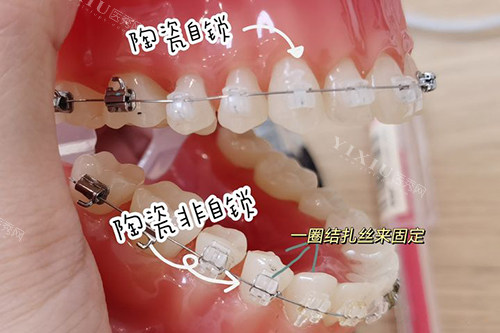

陶瓷自锁托槽矫正较大的亮点之一便是其出色的美观性。与传统的金属托槽相比,陶瓷托槽的颜色更接近牙齿本色,远远看去,几乎与牙齿融为一体,不会像金属托槽那样在口腔中显得十分突兀。对于那些对外观形象有较高要求,尤其是成年矫正者来说,陶瓷自锁托槽矫正能在矫正牙齿的同时,较大程度减少对日常社交和工作的影响,让他们在矫正期间也能自信地展现笑容。

陶瓷自锁托槽在设计上更加人性化。它采用了自锁结构,减少了结扎丝或橡皮圈对口腔软组织的刺激。在矫正过程中,患者不会频繁感到口腔被刮伤或磨破,降低了口腔溃疡等不适情况的发生概率。而且,自锁结构使得托槽与弓丝之间的摩擦力减小,牙齿移动更加顺畅,这不仅减轻了患者在矫正初期的疼痛感,还能在一定程度上缩短矫正周期,让患者更快地看到矫正结果。